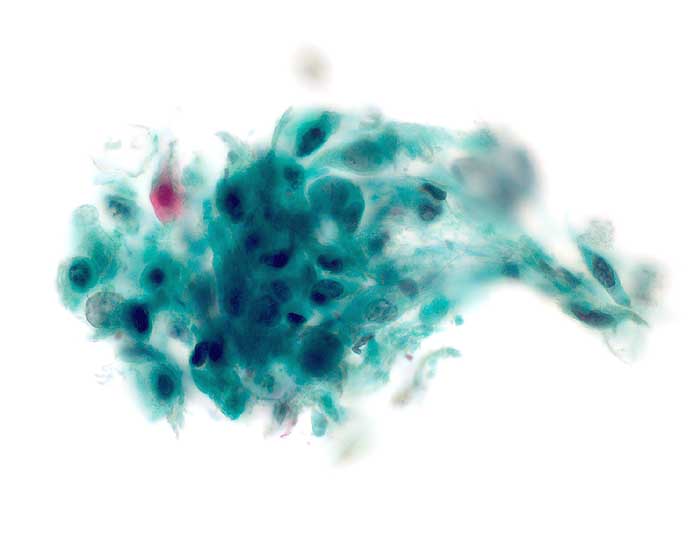

Die Tumorzellen liegen einzeln oder in kleinen Verbänden und ganzen Gewebsfragmenten. Die polymorphen Kerne sind vergrössert und enthalten verklumptes unregelmässig verteiltes Chromatin und grosse Nukleolen. Gut differenzierte Karzinome erkennt man am breiten und oft verhornten Zytoplasma. Längliche bis fadenförmige Tumorzellen mit pyknotischen Kernen können als einziger Hinweis auf das Vorliegen eines Karzinoms vorhanden sein. Wenig differenzierte Karzinome haben polymorphe und schlechter erhaltene Kerne. Der Hintergrund ist meist detritisch und oft hämorrhagisch. Ulzeration, Einblutungen und bakterielle Infektionen beeinflussen den Erhaltungszustand und die Art der abgestrichenen Zellen. Ist die Oberfläche eines ulzerierten Karzinoms von einem Fibrinschorf bedeckt, enthalten die Ausstriche lediglich Detritus, Granulozyten und Erythrozyten, aber keine Tumorzellen. Die Sensitivität für die Karzinomdiagnose ist aus diesem Grund geringer als für die Diagnose eines Carcinoma in situ.

Unten werden drei Fallbeispiele mit histologischer Korrelation gezeigt.